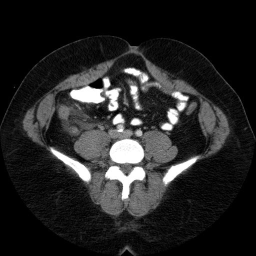

These are images from a contrast enhanced abdominal CT.

Fluid in the right paracolic gutter, and a thickened, inflamed appendix with thickening of the adjacent cecal wall.

Differential: Acute appendicitis is by far the most likely diagnosis.

No appendicolith is seen in this case.

The appendix is normally less than 7 mm in diameter, or if fluid filled, the wall can be up to 3mm thick. This appendix is distended, and the adjacent stranding and fluid indicates the inflammatory process which is causing peritoneal irritation and pain. Here is a series of images showing a normal appendix using similar technique. Note the thin walls of the normal appendix.